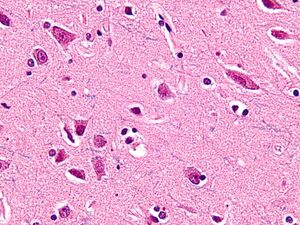

العصبونات المغزلية Spindle neurons، تسمى أيضاً عصبونات ڤون إكونومو von Economo neurons (VENs)، هم رتبة معينة من العصبونات التي تشارك في نقل الإشارات في الجهاز العصبي، وتتميز بجسم على شكل مغزل كبير، ينحف تدريجياً حتى يصبح محور عصبي وحيد القمة في اتجاه، ويصبح زائدة مشجرة dendrite واحدة في الاتجاه المقابل. وبينما الأنواع الأخرى من العصبونات تنحى لأن يكون لها العديد من الزوائد المشجرة، فإن الشكل القطبي للعصبونات المغزلية يـُعد فريداً، وقد تم العثور عليه فقط في منطقتين محدودتين في مخ hominids - الفصيلة التي تضم البشر والقردة العليا. وتوجد الخلايا المغزلية أيضاً في أمخاخ الحوت الأحدب، الحوت الزعنفي، الحوت القاتل والحوت المنوي[1][2], وفي أمخاخ الفيل الافريقي و الأسيوي.[3] الاسم عصبون ڤون إكونومو يحمل اسم مكتشفه، كونستانتين ڤون إكونومو Constantin von Economo (1876-1931).